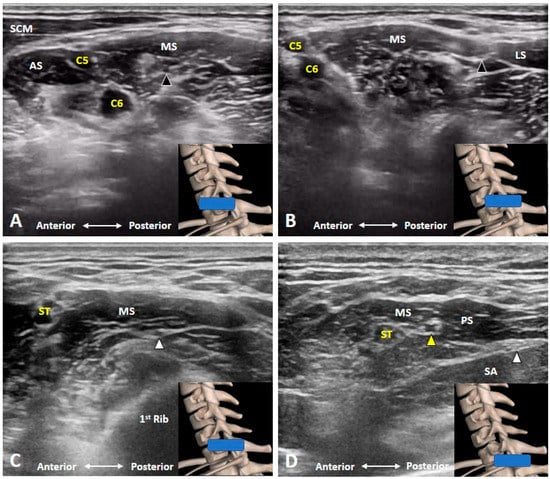

3.6. Which Branches of the BP Can Be Seen in the Cervical Region?